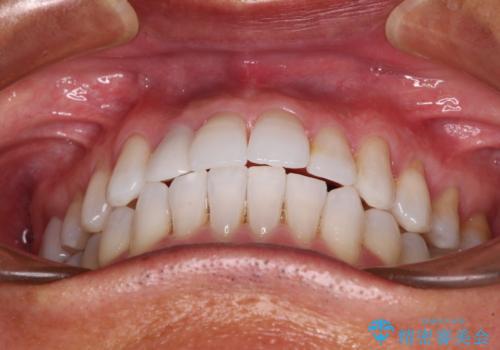

治療途中の前歯を治したい インビザライン矯正とオールセラミッククラウン

- 治療途中の前歯と上下前歯のデコボコ気にして来院された患者様です。

前歯のデコボコはインビザラインにより歯列を整え、その後に、前歯などをオーダーメイドタイプのオールセラミッククラウンにて補綴治療することとしました。

長時間のマウスピース装着に協力いただき、短期間で歯列をしっかりと改善することができました。

ホームホワイトニングを併用していただいたので、とても明るい口元に仕上がり、患者様には大変満足していただきました。